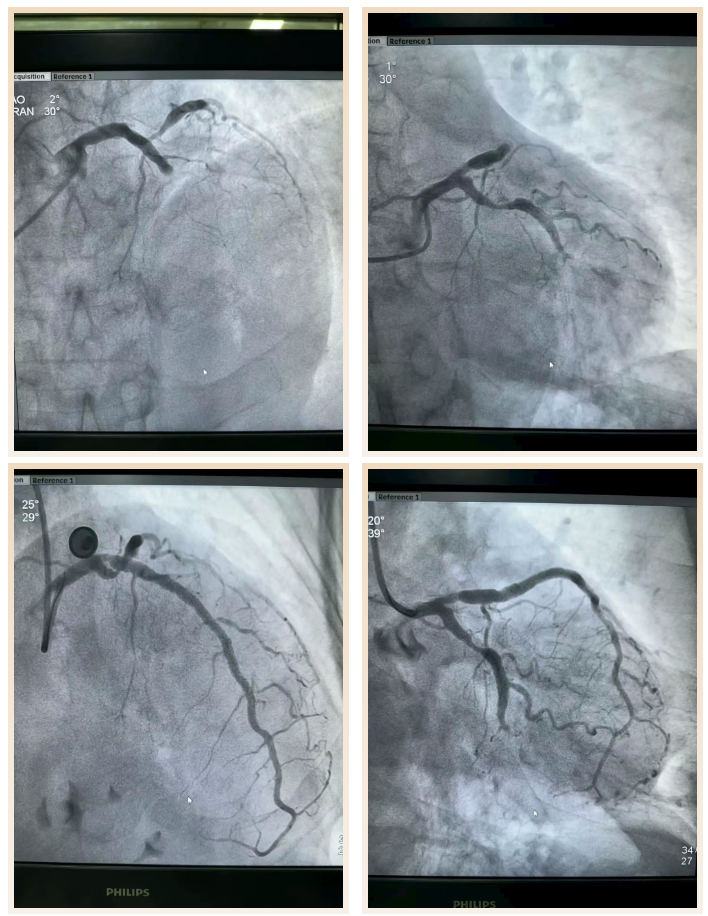

80岁的陈大爷因发作性呼吸困难紧急入院,急诊心电图检查提示前壁心肌梗死,病情危急,随时可能出现生命危险。杨俊杰第一时间赶到病房,结合患者症状与检查结果快速评估病情,判断需立即行冠脉造影检查明确冠脉病变情况。

造影结果显示,患者前降支完全闭塞且伴有钙化,这无疑为介入治疗增加了极大难度,钙化的血管壁质地坚硬,普通器械难以通过,手术操作稍有不慎便可能引发血管破裂等严重并发症。

“患者的生命容不得半点迟疑,再难也要上!” 杨俊杰与当地心内科介入团队迅速制定详细的手术方案,在术中反复尝试精准操作,小心翼翼地通过闭塞病变处,最终成功开通患者闭塞的前降支,恢复冠脉血流。术后患者呼吸困难症状明显缓解,各项生命体征逐步平稳,经过后续的精心治疗与护理,顺利康复出院。